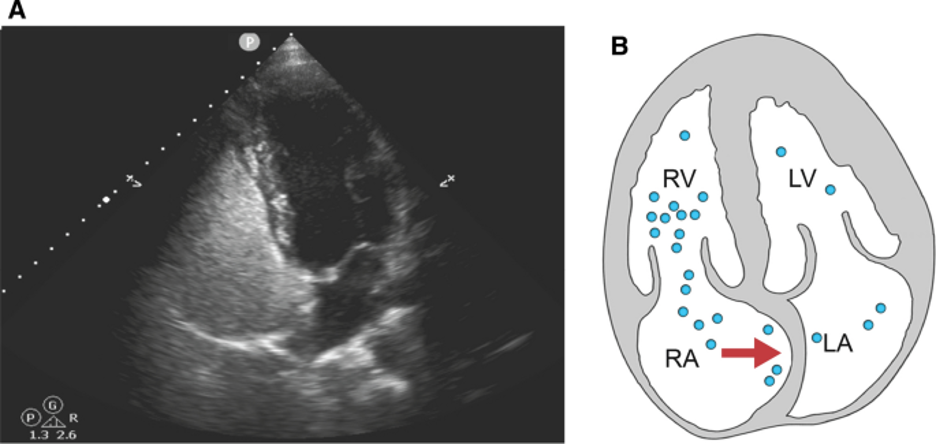

Because the microbubbles in agitated saline are too large to pass through pulmonary circulation, they provide a simple but powerful tool for detecting shunt physiology, as the passage of intact bubbles from the right to left heart most likely indicates a circulatory anomaly bypassing the pulmonary vasculature. In oriented patients, shunt enhancing maneuvers like Valsalva may be used to increase right atrial pressure and briefly exacerbate an existing shunt to improve sensitivity (see Figure 5). In obtunded patients, lung recruiting maneuvers such as briefly applying positive pressure ventilation may function similarly to Valsalva.

Figure 5:  Apical 4 chamber view on ultrasound (A) and schematic (B) during Valsalva demonstrating atrial septum bowing. Image from the Montrief et al’s review on POCUS for detection of right to left cardiac shunting(1).